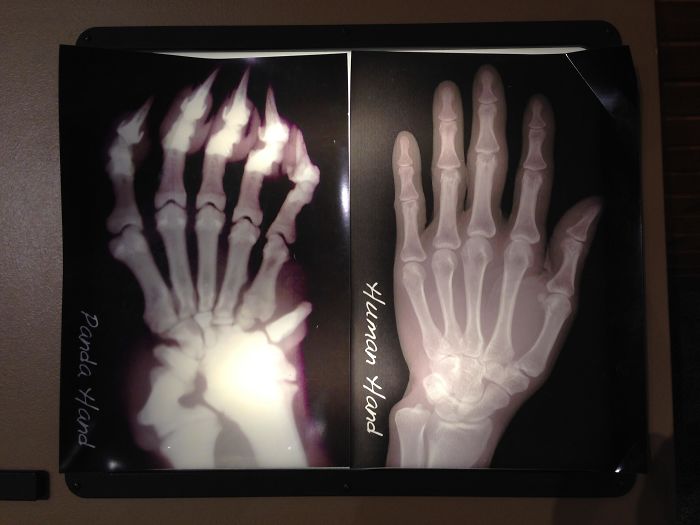

X-Ray Of A Panda Hand vs. A Human Hand; Pandas Have An Extra "Thumb" To Help Grip Bamboo Stalks

That is why the Giant Panda was named Panda after the Red Panda - the red one has these thumbs too, though for them it's to aid in climbing the bamboo.